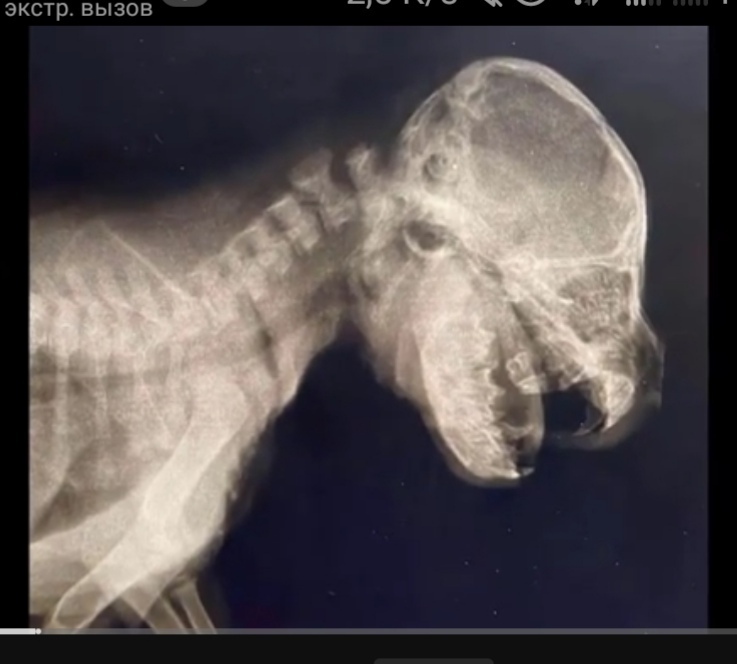

После дальнейшего расспроса, соседка раскрыла шокирующую правду, оказалось, что щенок украл овощную еду,

и в приступе агрессии, в порыве гнева, сосед вонзил металлическую иглу в боковую челюсть щенка!